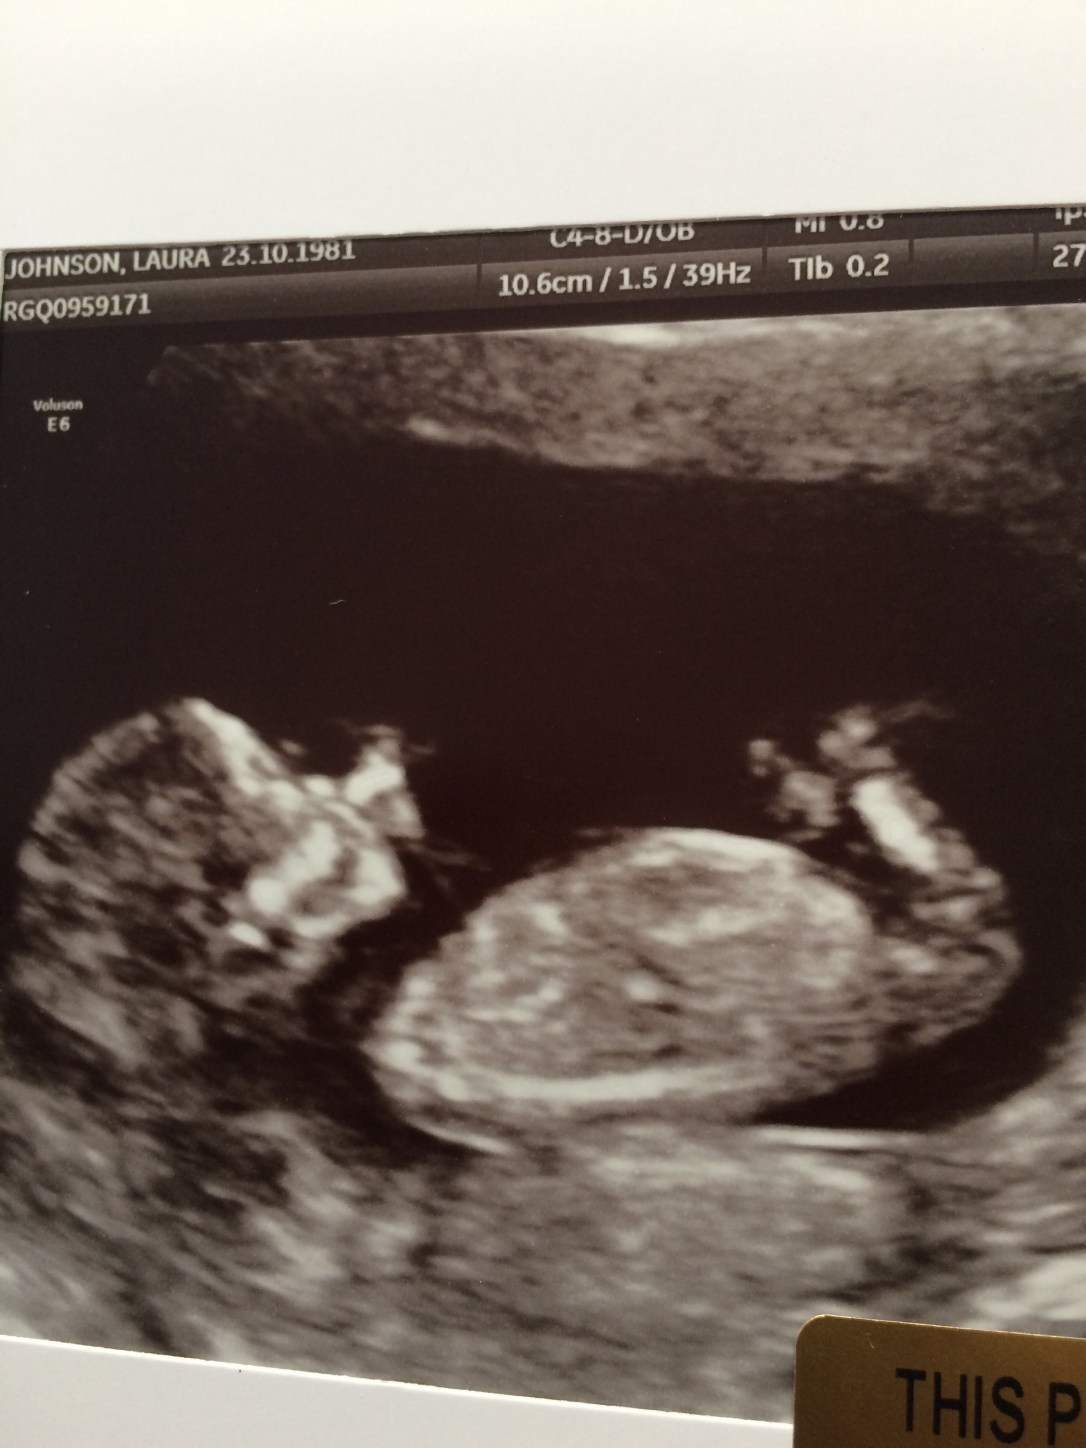

I’ve seen several new clients who’ve fallen in love with Bowen, Intro to Bowen parties have been a hit and enjoyed by hosts and guests, and we have a couple of clients who’ve sent me the exciting news that they’re ‘expecting’. Did you know that Bowen has been cited on several occasions as a contributing factor to conception? whether it’s due to reducing the females stress levels or making subtle changes to posture alignment I’m honestly not sure, but I know from my own pregnancy story there is definitely something in Bowen that assists in some ladies falling pregnant very quickly after treatment!!!